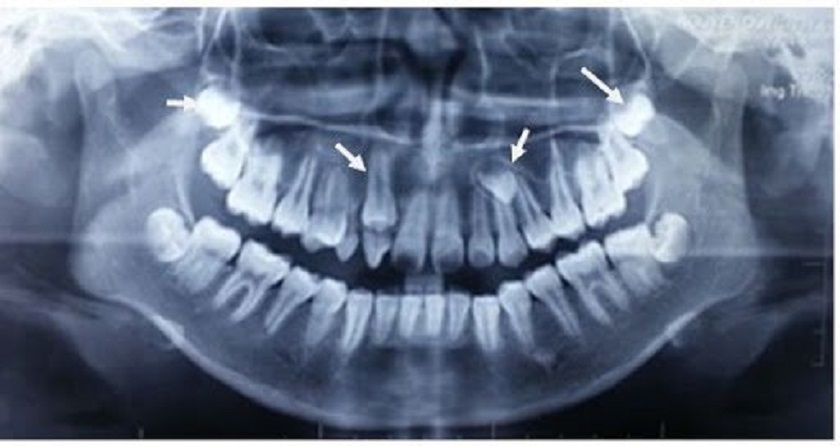

Hình ảnh răng mọc ngầm trên phim chụp X - quang

Răng mọc ngầm là tình trạng răng mọc bên trong xương hàm, chúng ta không thể quan sát hiện tượng này bằng mắt thường mà chỉ khi tiến hành chụp X – quang, các nang răng trong xương hàm mới có thể được phát hiện. Ngay cả bản thân người mắc đôi khi cũng không biết bản thân có răng ngầm nếu chiếc răng đó là răng thừa.